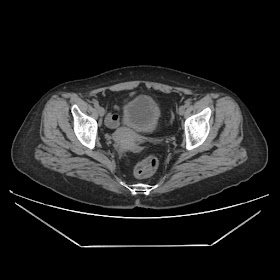

A CT abdomen revealed a left adrenal cortical tumor.

Her abdominal X-ray also reveals a right renal stone although she never complained of renal colic.

Clinician advised against surgery because she was not in pain. Her TSH is normal. A CT abdomen revealed a left adrenal cortical tumor. Diagnosis of pri. aldosteronism was made. Patient is hypertensive since 1995 since her second childbirth. Now BP is normal with medication. She is nondiabetic. Pt. advised to report her Ca2+ and K+ lvl. monthly. Pt. acq. the habit of eating paan (beetle leaf) from her mother in 2011 when she came to stay with her. Used to eat 3-4 paans a day. Stopped in 2013 after Dr. advised against it.

PATIENT'S HISTORY: The patient is a 60-year-old housewife. In 2013, she had an episode of probable stroke followed by nausea, vomiting, diarrhea, weakness, fatigue with loss of appetite, and insomnia. Her legs felt numb. She lost sensation around neck. Had to be admitted to a nursing home. Diagnosis of hypocalcemia and hypokalemia was made. Got discharged after 5 days when k+ and Ca2+ lvl. returned to normal via i.v infusion. For 2 yrs she was fine. In 2015, due to diarrhea and fatigue she got admitted to a Nursing home and stayed there for 7 days. Ca2+ and K+ lvl. was falling, so restored via i.v infusion. This time hypernatremia was also detected. Discharged after her conditions improved. But 2 days later, again due to severe diarrhea had to be admitted to a Nursing home for 19 days. During her stay USG of abdomen, colposcopy and chest X-ray was done. USG detected a large renal calculus measuring 22mm in rt. kidney. Sx was recommended. Pt went to Bhopal for a second opinion.